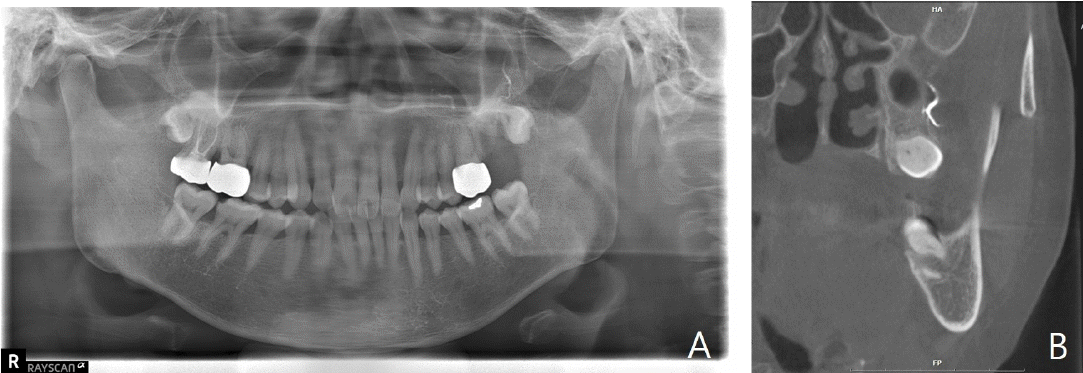

Fig. 6.

A. Panoramic radiograph taken approximately six weeks after the incident shows persistent radiopaque material in the periapical region, consistent with extruded calcium hydroxide. B. Coronal cone-beam computed tomogrpahic image demonstrates the presence of extruded calcium hydroxide within the adjacent soft tissue space.